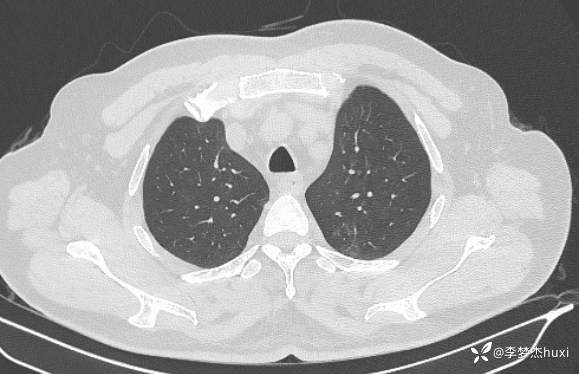

男性48岁,咯血3小时,咯血病因?

主诉:咯血3小时

简要病史:患者于入院前3小时无明显诱因出现咯血,为鲜红色,量较多,约10ml,伴胸闷、压气,伴咳嗽,无明显咳痰。

体格检查:T36.2℃,P110次/分,R20次/分,BP250/130mmHg。神清,呼吸平稳,浅表淋巴结不大,双肺叩清音,双肺未闻及干湿性啰音,心率110次/分,律齐,无杂音。腹部平坦,软,全腹无压痛,无反跳痛及肌紧张,肝脾肋下未触及,双下肢无水肿。

辅助检查:胸部CT:双肺炎症,双肺纹理增多,主动脉及冠状动脉钙化,主肺动脉稍增粗,右侧肾上腺点状高密度影,考虑脂肪肝。

临床诊断:肺炎咯血